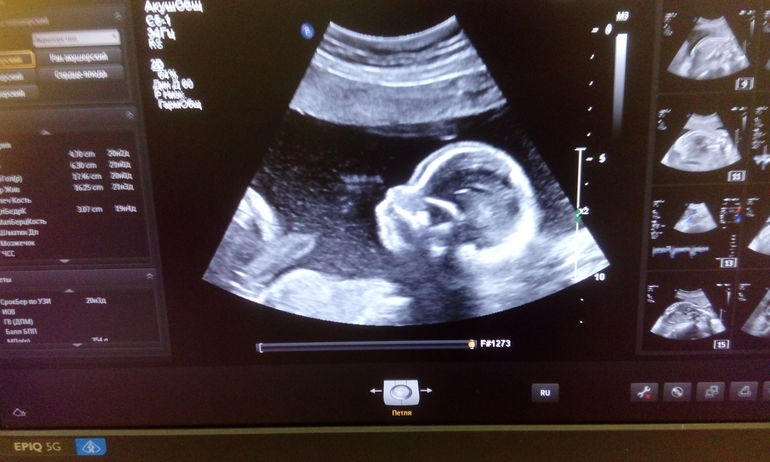

В пятницу прошла второй скрининг. Все хорошо. Можно перекрасить уже значок в синий цвет )) Заключение (кому интересно) и фото выложу ниже ))

Даа, спасибо! )) Особенно смешно сравнивать снимок с младшими, когда они мультики смотрят открыв рот - один в один профиль )))